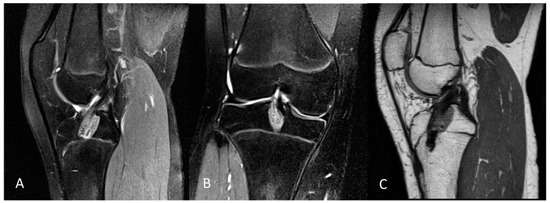

This retrospective study included skeletally immature patients presenting with full-thickness ACL tears, confirmed by MRI and intraoperative evaluation. Patient examples are shown in Figure 1.

Figure 1.

Example of a 3.0 Tesla knee MRI: (A) coronal PD tse fs, (B) sagittal T2 tse, and (C) conventional X-ray in AP view of 14-year-old male patient with open physis and acute ACL rupture. PD tse fs (proton density-weighted turbo spin echo sequence with fat saturation), T2 tse (T2-weighted turbo spin echo sequence), ap (anterior–posterior); large arrow is ACL rupture; star is bone marrow edema.